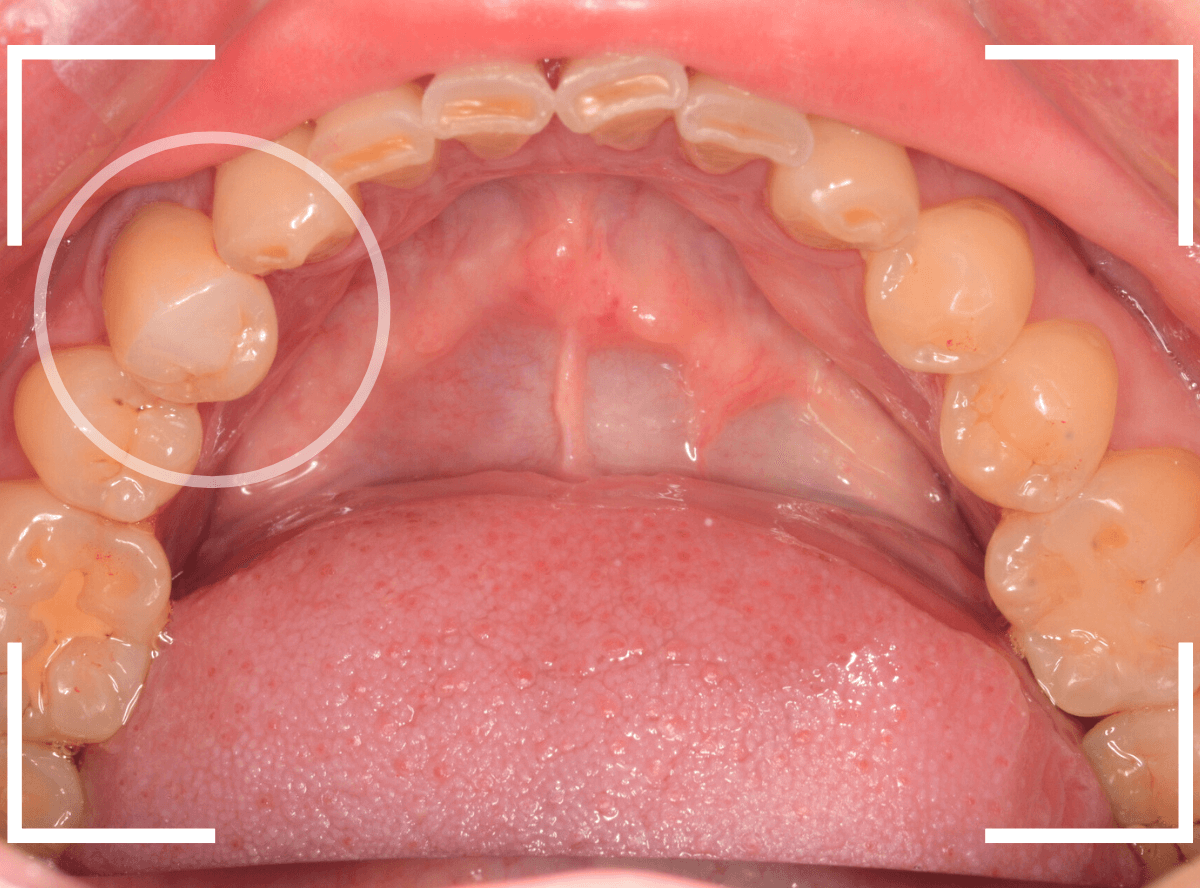

歯の神経の治療後、土台まで作って長期間放置してしまった方です。

このような方は多く見受けられます。

ご本人には「痛くもないし、少し咬みづらい」くらいの感覚かもしれませんが、この状態で放置すると、歯はない方に動く習性がありますので、咬み合わせる反対の歯がずれてきてしまい、さし歯を作る際の支障になってしまいます。

この方も、反対の歯が大分ずれてきてしまいましたので、歯を大きく削る必要があり、調整に苦労しました。

模型上で精密に製作します。

最終setした状態です。

通常よりかみ合わせの調整もに苦労しましたが、何とか無事にset出来ました。